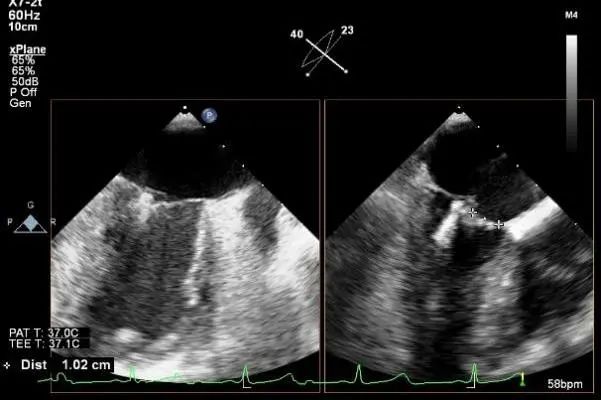

Bicaval 寻找穿刺点

穿刺点距离二尖瓣环3.42cm

房间隔穿刺

穿刺点距离二尖瓣环4.6cm